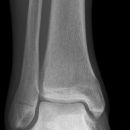

Sprunggelenk